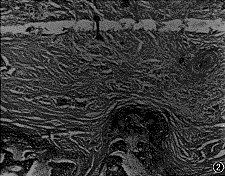

图2 髁突纵行骨折后6个月小型猪TMJ组织学切片,盘突粘连组织内可见血管、大量成纤维细胞、血管及散在的软骨细胞。关节盘胶原纤维排列呈旋涡状,内含大量脂肪细胞,可见血管(HE×4)

3.纵行骨折组:骨折后3个月见盘突粘连明显,粘连部位与周围组织的界限不清,粘连区由纤维结缔组织组成,内含大量的软骨细胞,部分粘连区纤维结缔组织与骨小梁紧密结合(图1)。关节盘纤维排列紊乱,出现血管及脂肪细胞。骨折后6个月镜下观察:粘连组织内可见血管、大量的成纤维细胞及散在的软骨细胞。关节盘胶原纤维排列呈旋窝状,内含大量脂肪细胞并可见血管(图2)。在未粘连部位可见髁突表面纤维软骨增厚,表面纤维排列紊乱。关节盘表面呈增生改变。